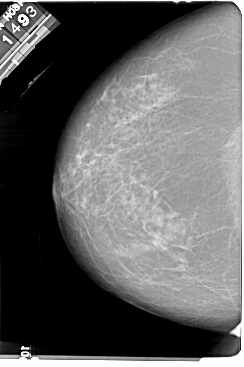

A_1858_1.RIGHT_MLO

RIGHT_MLO LINES 5491 PIXELS_PER_LINE 3811 BITS_PER_PIXEL 12 RESOLUTION 43.5 OVERLAY